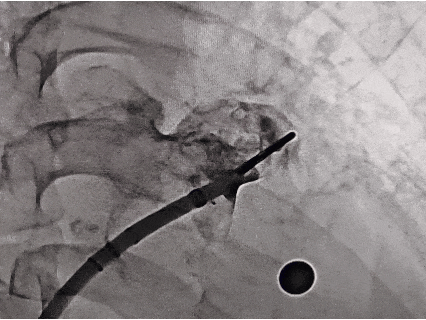

DSA下肝位造影+测量

肝位测量,开口26.13 mm,深度29.65 mm